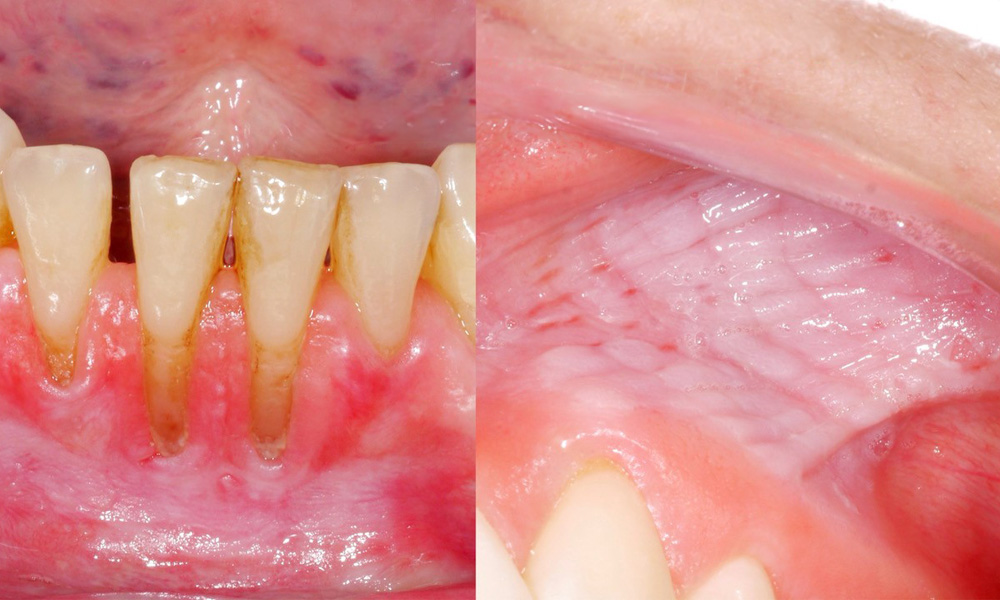

The clinical examination showed that regular consumption of snus can have the following effects on the oral mucosa:

- Approximately 80% of those examined who consumed snus daily had snus-induced mucosal lesions.

- For each additional tin of snus consumed per month, the risk of a more severe mucosal lesion increased significantly.

- Approximately 20% of those examined who consumed snus daily had snus-induced gingival recession.

- For each additional year that snus was consumed, the risk of snus-induced gingival recession increased significantly.